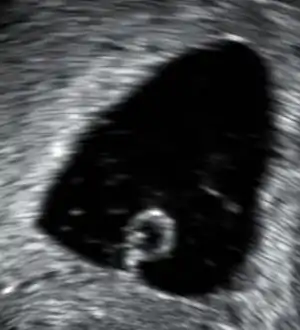

An ultrasound showing a gestational sac containing a yolk sac but no embryo.

An anembryonic pregnancy (also called an "empty sac" or "blighted ovum") is a condition where the gestational sac develops normally, while the embryonic part of the pregnancy is either absent or stops growing very early. This accounts for approximately half of miscarriages. All other miscarriages are classified as embryonic miscarriages, meaning that there is an embryo present in the gestational sac. Half of embryonic miscarriages have aneuploidy (an abnormal number of chromosomes).[48]